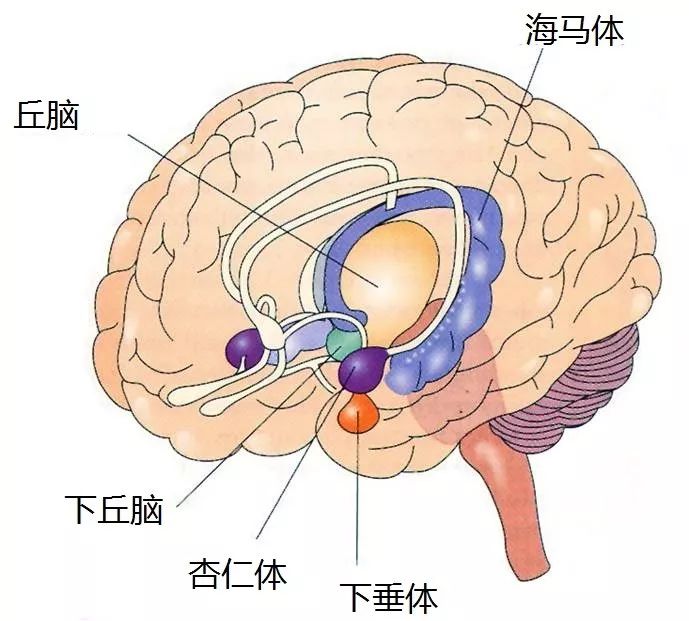

古哺乳动物脑: 边缘系统

脑干上方的就是边缘系统,也正是边缘系统让人类如此神经质 。

不管如何,我们还是要仔细看看边缘系统。边缘系统里面有很多小组件,我们这里就只关注那些最重要的啦:

杏仁体就是人类情绪的车祸现场。杏仁体负责焦虑、悲伤以及对恐惧的反应。杏仁体有两个,很奇怪的是,左边的那个更加平衡,有时会在负面情绪外产生一些正面感觉,但是右边那个杏仁体却一直是在糟糕的情绪中的。

海马体就好像记忆的草稿本。当老鼠开始记忆迷宫中的方向的时候,它们的记忆就是被编码存储在海马体里的。处在迷宫中的不同位置的时候,老鼠的两个海马体的不同部位会各自产生不同的反应。但是如果在记住一个迷宫之后,这只老鼠又被派去干了些别的任务,在一年后再把这只老鼠放回原本的迷宫中,它就很难记得迷宫的方向了。这是因为海马体这个草稿本上的记忆很多被擦除掉,从而腾出空间来给其它新的记忆了。

电影《记忆碎片》中主角的症状是真实存在的一种病,叫作顺行性遗忘症。这种症状就是海马体的损害导致的。阿尔兹海默症也是从海马体开始发病,然后蔓延到脑的其它部位,所以在阿尔兹海默症的所有症状中,记忆力衰退是最早出现的。

丘脑位于整个脑的中间位置,干的也是感官信息中间人的角色。丘脑接收到感官器官发来的信息,然后把信息传递到皮质去处理。当你睡着的时候,丘脑也会入睡,也就意味着传递感官信息的中间人下班了。所以在沉睡的时候,声音、灯光、触摸有时不会把你唤醒。如果你想要把一个沉睡的人唤醒,动作要激烈到把他的丘脑唤醒。

这里唯一的例外是你的嗅觉,嗅觉是唯一不经过丘脑的感官。所以给昏迷的人闻盐是一个常用的唤醒手段。顺带一提,嗅球(olfactory bulb)是最古老的感官。与其它感官不同,嗅觉位于边缘系统的深处,和海马体与杏仁体合作紧密,所以嗅觉才会与记忆和情绪紧密关联。